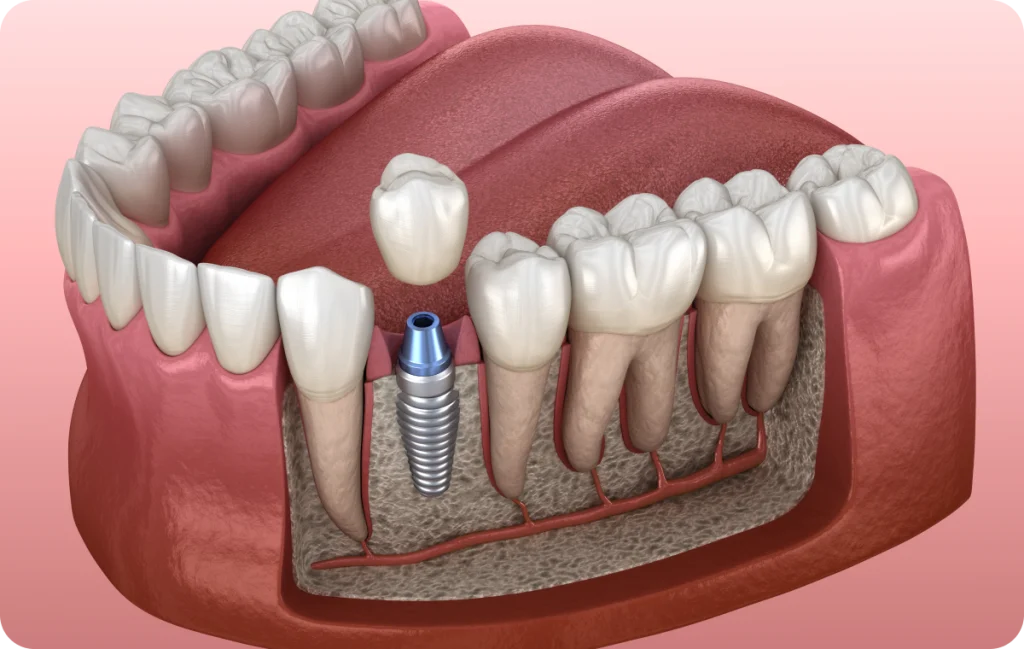

Un implant dentaire permet de remplacer une dent absente de manière durable. Concrètement, il s’agit d’une racine artificielle, le plus souvent en titane, que le praticien insère dans l’os de la mâchoire.

Cette racine accueille ensuite une dent prothétique, appelée couronne, qui reproduit l’apparence et la fonction d’une dent naturelle. Ainsi, l’implant dentaire participe à la restauration de la mastication, de l’équilibre de la denture et de l’esthétique du sourire.

Contrairement à d’autres solutions, l’implant dentaire ne prend pas appui sur les dents voisines. De ce fait, il permet de préserver leur intégrité. Par ailleurs, l’implant transmet les forces de mastication à l’os, ce qui contribue au maintien du volume osseux. Cette stimulation joue un rôle important dans la stabilité de la mâchoire sur le long terme.

La pose de l’implant dentaire se déroule sous anesthésie locale. Le praticien insère l’implant dans l’os en respectant un protocole précis. Cette intervention reste généralement bien tolérée et ne dure que peu de temps.

Après la pose, une phase de cicatrisation débute. Pendant cette période, l’implant s’intègre progressivement à l’os grâce au processus d’ostéointégration. Cette étape nécessite plusieurs semaines, voire quelques mois, selon la situation clinique.

Une fois l’implant solidement intégré, le praticien procède à la mise en place de la couronne. Celle-ci est fabriquée sur mesure afin de s’harmoniser avec les dents naturelles. Ainsi, elle respecte la forme, la couleur et la fonction de la dent remplacée.